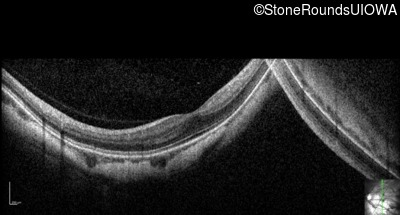

Optical Coherence Tomography - Left - 20/30

Exemplar / OCT Stack

OCT Stack